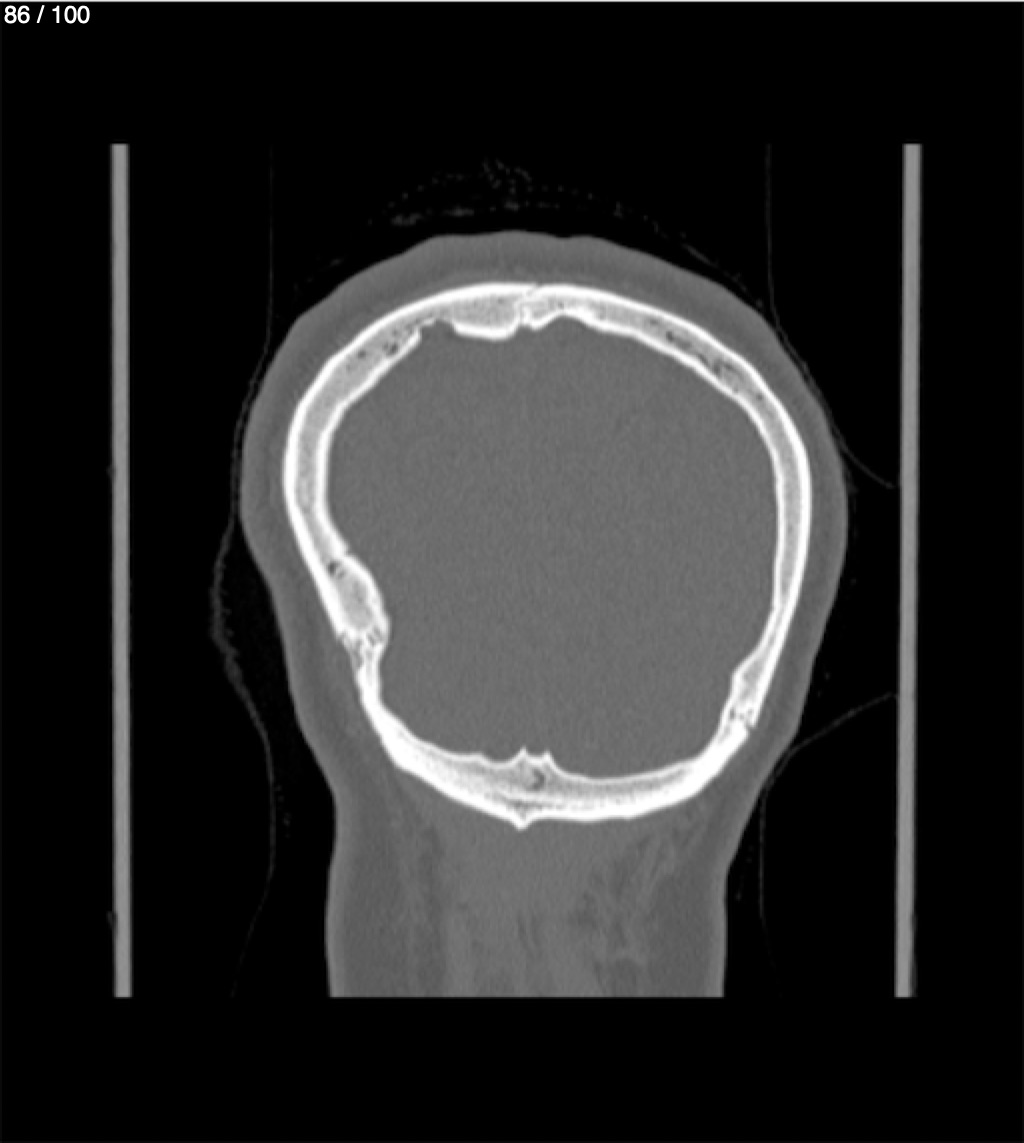

Yonelly Barrios Diaz 35A - T.C Craneo